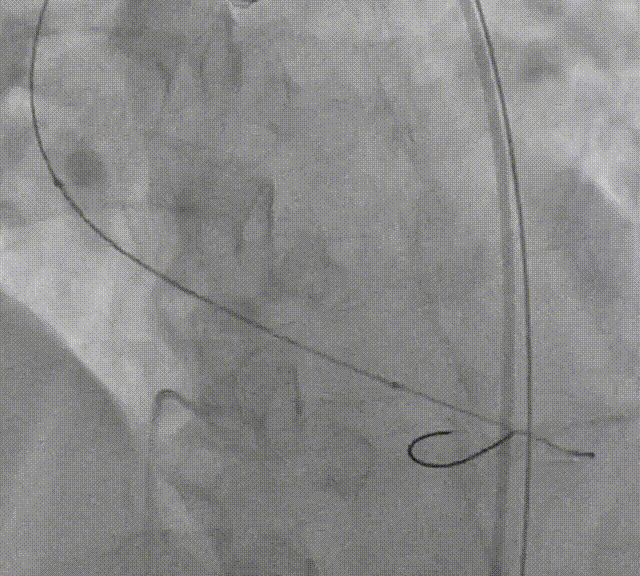

球囊预扩张

10mm*10cm小球囊预扩

23mm Z-Med预扩张

根据预扩表现决定使用26mm瓣膜